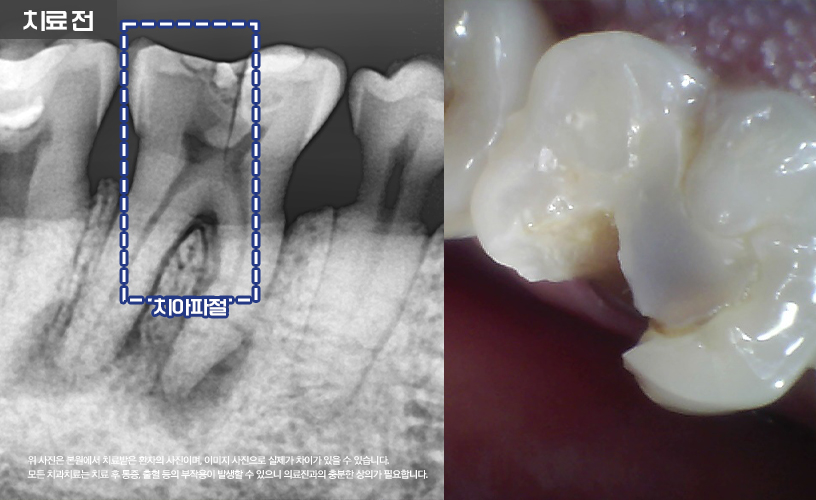

"치아 파절 치료 사례"

상기 환자분은 치아 파절로 인해

본 원에 내원하시어 치료한 사례입니다.

환자분의 경우 어금니 부분에 크랙이 있으신 상태로

지내시다가 균열이 점점 커지고 치아 뿌리까지

염증이 심해져 치아가 파절되었습니다.

보다 자세한 상태를 확인하기 위해

정밀한 검진이 이루어졌습니다.

환자분의 경우 치근단병소로 인해

치조골이 소실되어 있는 상태였습니다.

이런 경우 발치 및 염증 제거 치료가

먼저 진행되었습니다.